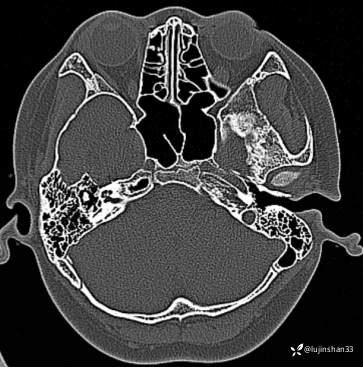

【主诉】:检查发现右侧颅中窝肿物3月

【现病史及既往史】:患者3月前头部磕碰后感疼痛,当时被老师送到XX市XX县人民医院,行CT检查提示颅内肿物,又继续到XX省第二人民医院行头颅核磁示:右侧颅中窝肿物,建议手术治疗,于7月23日入住我科拟行手术,但患儿极度不配合,办理出院回家调整,现完善心理建设,要求手术。

【临床诊断】:颅底占位